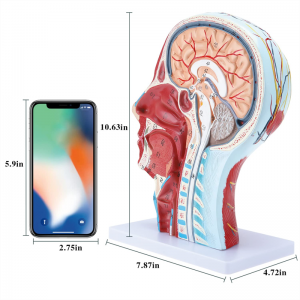

Human Half Head & Neck Anatomy Model Superficial Neurovascular Model

Human Half Head & Neck Anatomy Model Superficial Neurovascular Model

| Product Name | Human skull with muscle neurovascular model |

| Material | PVC |

| Dimension | 21*12*27cm |

| Features | The model shows the local morphology of the inner and outer sides of the Median sagittal section of the head and neck, as well as the structures of blood vessels and nerves, and there are 84 parts indicating signs in total. |

【1:1 Lifesize】Median Section of 1:1 natural large head & neck superficial neural vascular muscle model (right side). Fine workmanship. Offering a full range of anatomical features.

【High Quality】Brain anatomy model, made of non-toxic environmentally friendly PVC material, easy to clean. Anatomy models are hand-painted and assembled with the utmost attention to detail.

【Superficial Neurovascular Muscle Model】Highly detailed, numbers marked, detachable ear, deepen the understanding of the superficial muscles, vessels, nerves and the internal structures of the head & neck. Red-artery, blue-vein, yellow-nerve.

【Features】It shows the superficial muscles of the exposed face; the superficial blood vessels & nerves of the face & scalp; the inner structures of parotid gland & upper respiratory tract; the sagittal cross-section structure of the cervical spine.

【Application】This model is the first choice for the doctor's office, school, hosipital and clincs. Really a great teaching aid for anatomy & physiology courses, demonstration, communication tool for doctors and patients.

This model shows details of the right head neck and mid sagittal section of the human. including the superficial

muscles of the exposed face; the superficial blood vessels and nerves of the face and scalp; the inner structures

of parotid gland and upper respiratory tract; the sagittal cross-section structure of the cervical spine.

The model showed the local morphology of the medial and lateral sagittal sections of the head and neck and its vascular and nerve structures, with a total of 100 site indicators.

This model is a natural large head and neck superficial neurovascular muscle model, 1 component, showing the details of the human right head and neck and median sagittal section, including the exposed superficial muscles of the face, superficial vessels of the face and scalp, nerves and the medial structure of the parotid gland and upper respiratory tract, and the sagittal section structure of the cervical spine